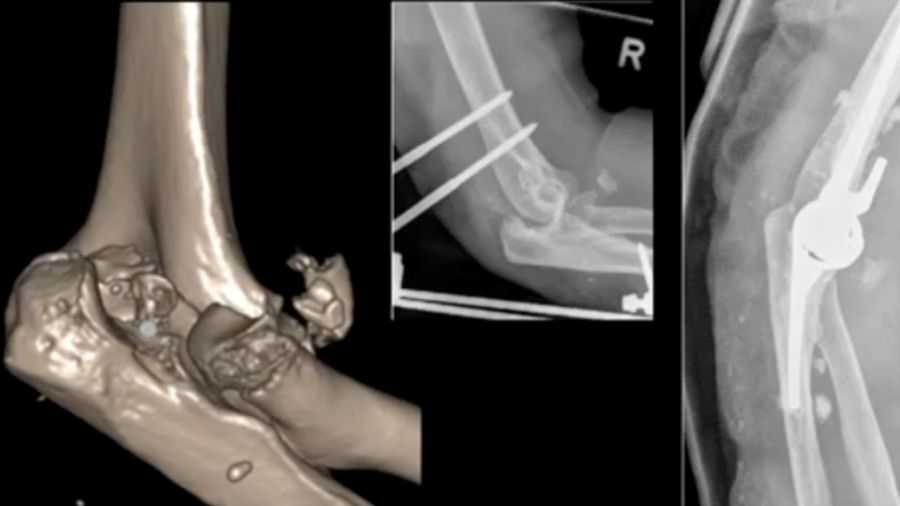

Case 3: 88-year-old woman

An 88-year-old patient with a terrible triad had an external fixator placed. A cemented prosthesis was chosen due to her age but encountered complications with cement leakage. Thankfully, no neurovascular damage occurred.

Case 4: 94-year-old woman

In this case, a total elbow prosthesis was chosen for a 94-year-old patient with severe trauma. The prosthesis was repositioned but eventually dislocated again, highlighting the complexities of managing such advanced injuries in older patients.